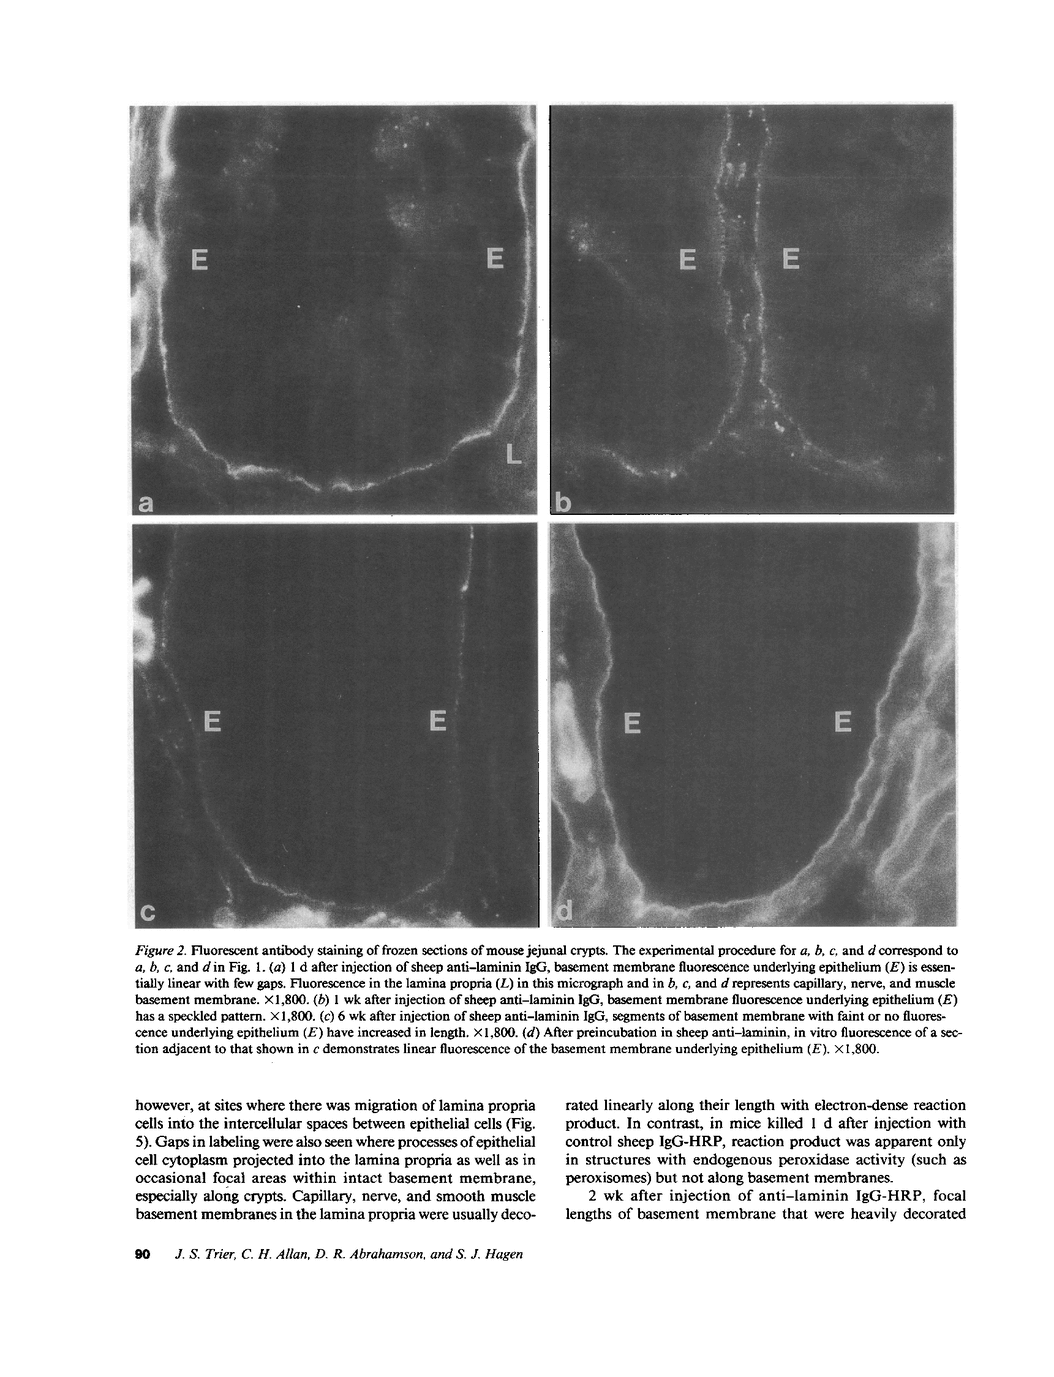

Little is known regarding turnover of the epithelial basement membrane in adult small intestine. Are components degraded and inserted along the length of the crypt-villus axis or selectively in the crypt region with subsequent migration of basement membrane from crypt to villus tip in concert with epithelium? We injected affinity-purified sheep anti-laminin IgG or sheep anti-laminin IgG complexed to horseradish peroxidase (HRP) into mice to label basement membrane laminin in vivo. Fluorescence microscopy revealed linear fluorescence along the length of the jejunal epithelial basement membrane 1 d after anti-laminin IgG injection. By 1 wk, small nonfluorescent domains were interposed between larger fluorescent domains. Over the next 5 wk the lengths of nonfluorescent domains increased progressively whereas those of fluorescent domains decreased. Additionally, electron microscopy revealed HRP reaction product along the length of the epithelial basement membrane after 1 d whereas unlabeled or lightly labeled domains that increased in length with time were observed interposed between heavily labeled domains by 2 and 4 wk along the entire crypt-villus axis. We conclude that laminin turnover occurs focally in the epithelial basement membrane of mouse jejunum along the crypt-villus axis over a period of weeks and that this basement membrane does not comigrate in concert with its overlying epithelium.